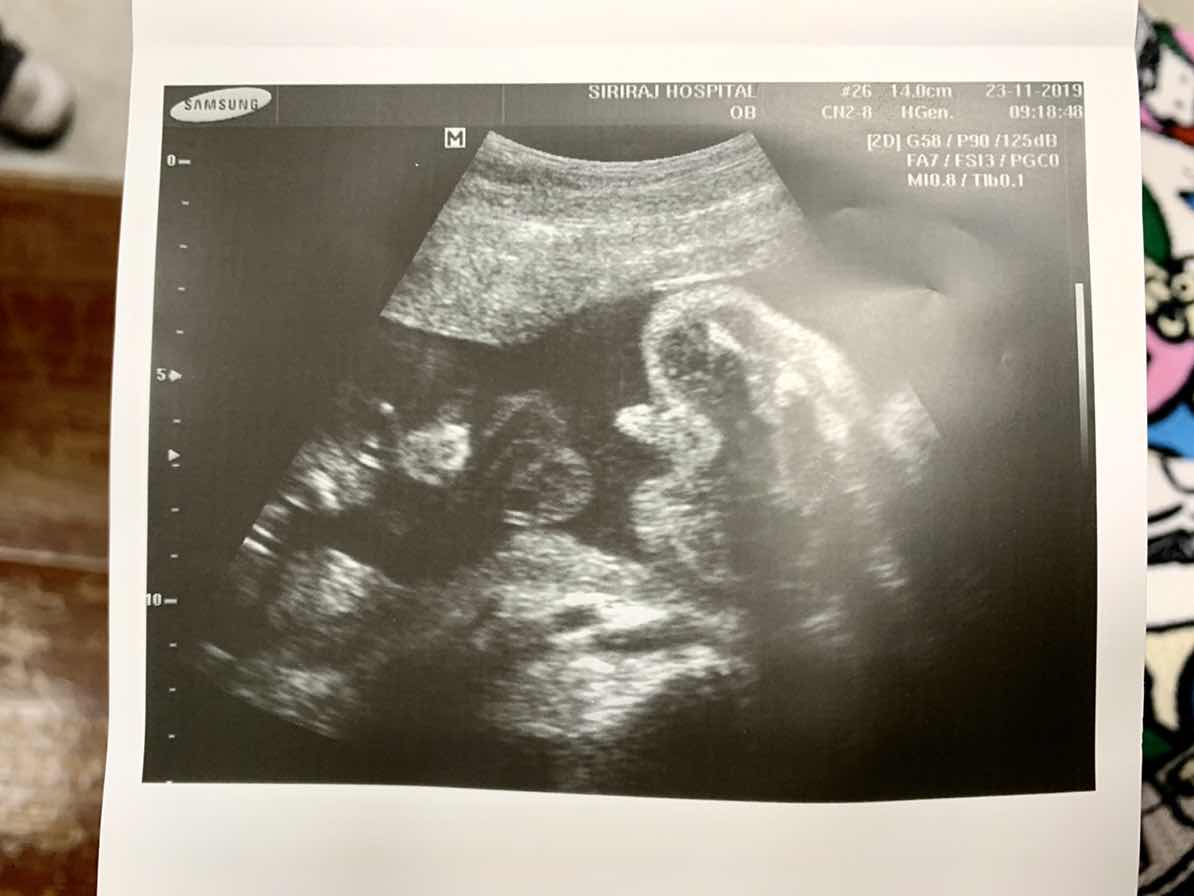

อวดรูปอัลตาซาวด์กันคะ

บ้านนี้รู้เพศตอน16สัปดาห์คะ ได้ผู้ชาย ปัจจุบัน21สัปดาห์6วันจ้า แม่บ้านอื่นได้เพศอะไรกันคะ มาอวดรูปแผ่นอัลตาซาวด์หน่อยจ้า ❤

รู้เพศตอน 16 สัปดาห์ ซาวด์ละเอียดตอน 19 สัปดาห์ ตอนนี้ 25 สัปดาห์ ลูกสาวจ้าา